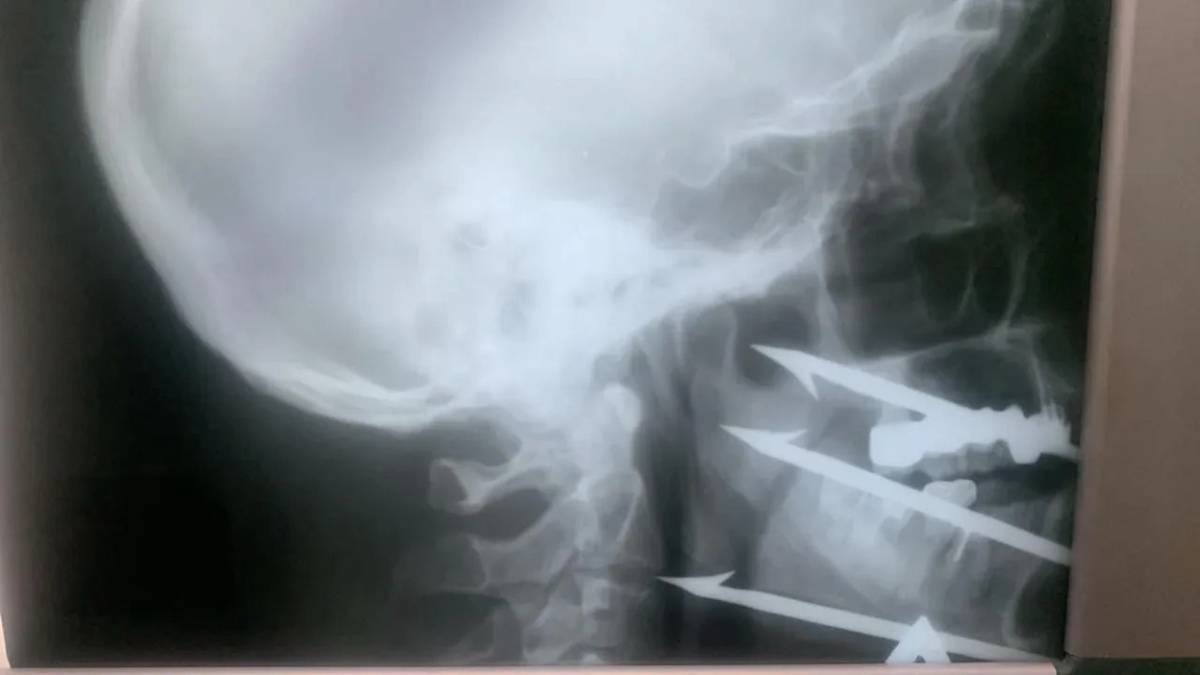

Хирурги Волгоградской городской клинической больницы № 1 спасли 52-летнего мужчину, который выстрелил себе в лицо трехзубым гарпуном во время подводной ловли рыбы. Предмет благополучно извлекли, и врачам удалось сохранить критически важные сосуды и нервы. Об этом в среду, 3 декабря, сообщили в пресс-службе Министерства здравоохранения региона.

— Ситуация была критическая: инородное тело остановилось в миллиметре от сонной артерии. Любое неосторожное движение или смещение могло привести к гибели, — говорится в сообщении.

Операцию проводили врач челюстно-лицевого отделения больницы № 1 Роман Стасюк, которого в этом году признали лучшим хирургом Волгоградской области, и сосудистый хирург больницы № 25 Олег Виноградов.

Сейчас жизни пациента ничего не угрожает, но ему предстоит пройти курс реабилитации, передает страница ведомства в соцсети «ВКонтакте».